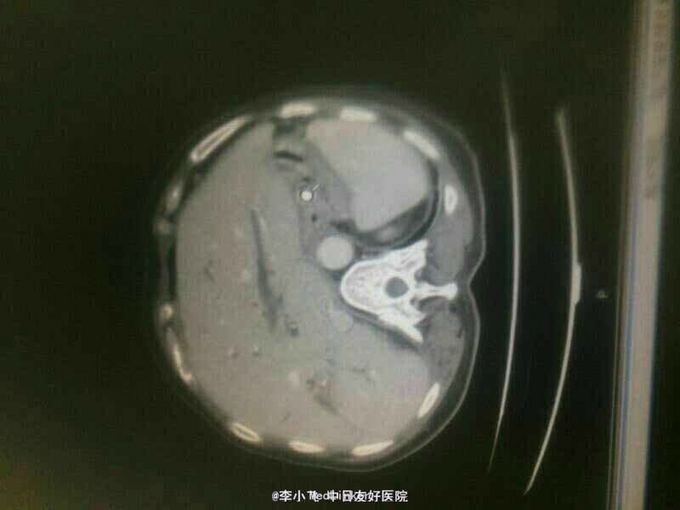

男性,50岁。右上腹胀痛半月,皮肤巩膜黄染10天入院 患者10天前进食后出现右上腹胀痛,平卧加重,伴后背放射痛,未重视。10天前出现皮肤巩膜黄染,就诊于当地医院,查腹部超声提示胆管扩张,胆管内占位性病变,为行进一步治疗入院。 既往史有高血压10年。血压控制可,余无特殊。

查体,生命体征平稳。右上腹压痛明显,剑突下轻压痛,无反跳痛。全腹未及明显包块。 腹部CT提示,肝内胆管扩张,肝外胆管内占位。

患者中年男性,右上腹不适,有黄疸,超声提示肝内胆管扩张,需要除外肝外胆管内占位性病变。 虽然胆囊结石一般不会导致胆管扩张,但当胆囊颈结石压迫胆管时,同样可出现肝内胆管扩张。